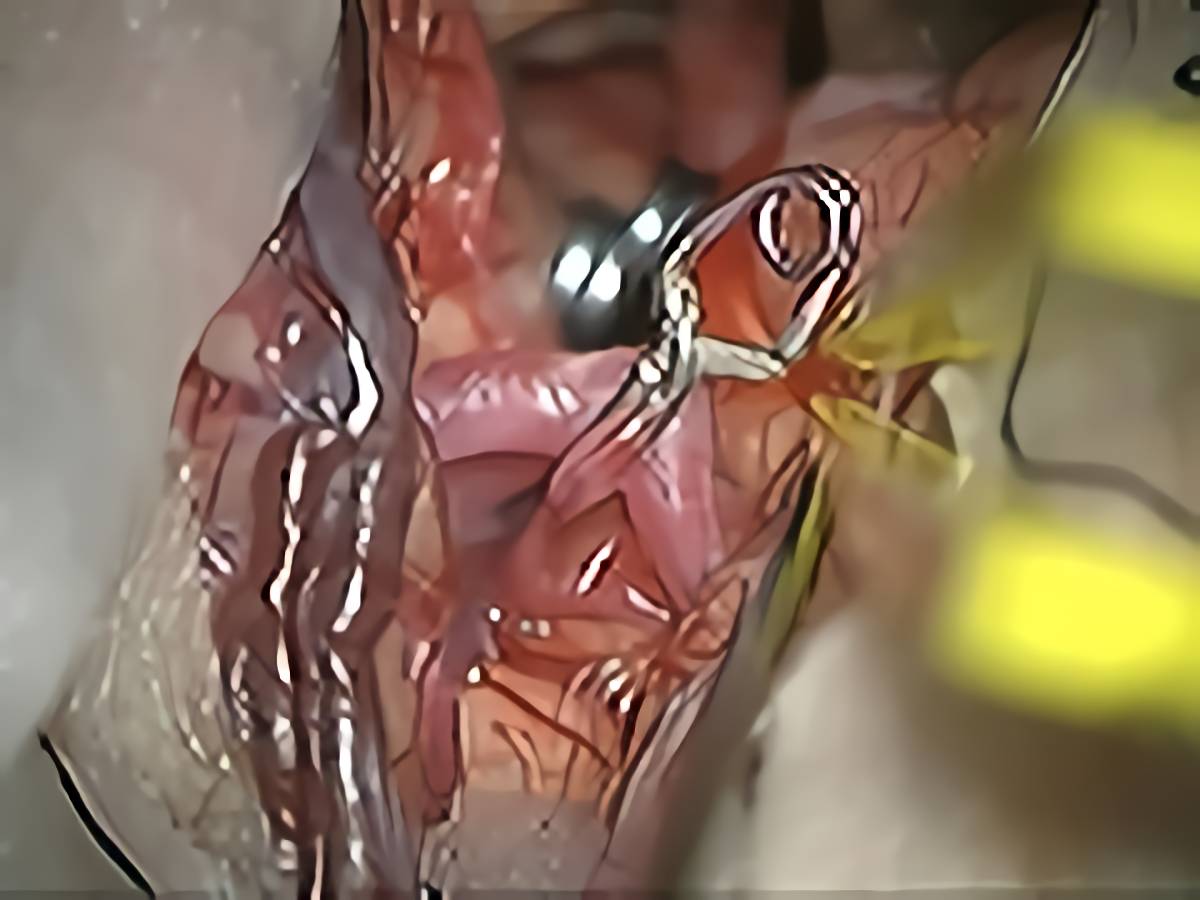

症例 '13年4月

No.

75

'13年4月

60代

脳底動脈、中大脳動脈

クリッピング術

クリップ前

クリップ後